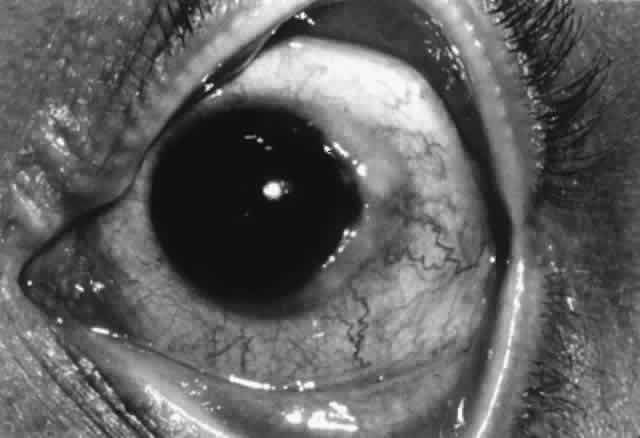

In the United States, about 40,000 persons per year undergo corneal transplantation.129 The majority of cases will do well, with only 10% or so of those recipients with avascular (low-risk) host corneas experiencing graft failure, whether HLA-matched or not.130 The main factor for this success is the “immune privilege” of the cornea, as previously discussed. However, in the subset of high-risk patients (i.e., those with previous graft rejection or vascularization in more than two quadrants), the risk of failure climbs to 35% to 65%.131–134 The major cause of corneal graft failure in these high-risk patients is immunologic allograft rejection, which occurs in about 50% of cases.

Mechanism of Corneal Graft Rejection

The mechanism of corneal graft rejection is classically believed to be a type IV cell-mediated immune reaction. Foreign class II antigens act as a strong stimulus and can be recognized by host helper T cells (CD4+ ). Also, host Langerhans cells process foreign class I antigen and present it in conjunction with self-class II molecules to host helper T cells.135 The result of either mechanism is helper T-cell activation.